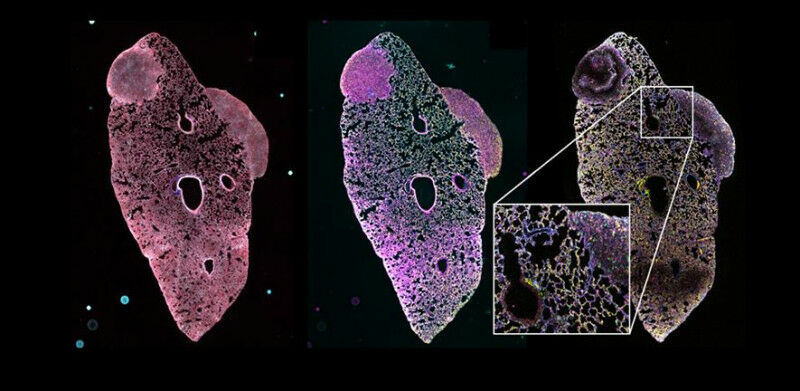

Top: Lung with two metastatic lesions derived from a mouse primary triple-negative breast tumour. The figure shows how the registration of the different imaging modalities to a cellular level allow to segment individual cells and identify tumour cell populations, differentiate hypoxic areas, increased fibrosis, infiltration of immune cells and blood and lymphatic vessels by staining with a panel of 35 cell markers at the same time. Bottom: Sample in 3D depicts a tumour grown in the mammary gland of a mouse showing the power of the SPACE pipeline to produce and visualise large volumes (typically ~100,000 individual images registered and stitched and up to 500TB 500 GB of data). The orange fluorescence beads are clearly visible in the medium outside the biological tissue and prove to be crucial for all stages of multimodal registration.

Dr Dario Bressan, Head of the SPACE Laboratory at the Cancer Research UK Cambridge Institute, said: "Tumours aren’t just a uniform mass of cells; they consist of a diverse ecosystem of cancer cells, immune cells, and other essential components that support their survival. Hidden within these intricate networks lies valuable information which could guide us in making more personalised treatment decisions for each patient.

"With the SPACE platform, researchers can zoom into specific cell populations, highlight the complex connections between them, and even run virtual experiments to predict how the tumour might respond to different treatments. By unlocking these insights, we can transform the future of cancer care and uncover new opportunities for targeted therapies."